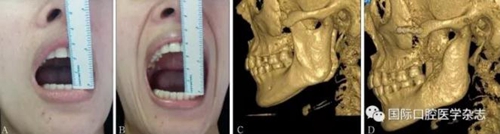

頜面部上下頜骨、顴骨及顴弓骨折、骨折片移位壓迫咀嚼肌群和下頜骨喙突,影響下頜骨的活動(dòng),一般采取手術(shù)治療復(fù)位骨折斷端,恢復(fù)下頜正常運(yùn)動(dòng)。頜面部腫瘤侵犯咀嚼肌群引起張口受限,一般行手術(shù)治療切除病灶(圖20)。

A:術(shù)前開口度;B:術(shù)后開口度;C:術(shù)前影像學(xué)檢查片;D:術(shù)后影像學(xué)檢查片。

圖 20 顴弓骨折修復(fù)術(shù)前后對(duì)比